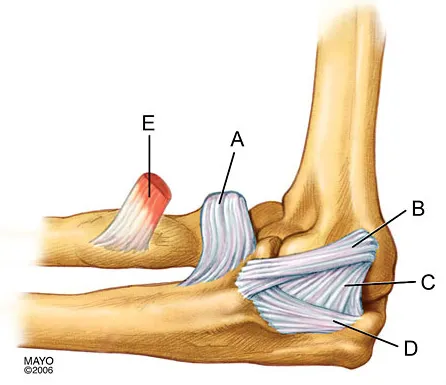

In Figure 2, which of the following structures is the primary stabilizer in preventing valgus instability of the elbow?

The lateral ulnar collateral ligament (LUCL) is the primary stabilizer against posterolateral rotatory instability (PLRI) of the elbow. Where does the LUCL typically insert?

Explanation